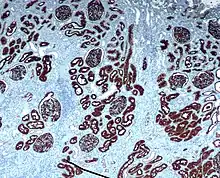

The renal cortex is the outer portion of the kidney between the renal capsule and the renal medulla.[1] In the adult, it forms a continuous smooth outer zone with a number of projections (cortical columns) that extend down between the pyramids. It contains the renal corpuscles and the renal tubules except for parts of the loop of Henle which descend into the renal medulla. It also contains blood vessels and cortical collecting ducts.

The renal cortex is the part of the kidney where ultrafiltration occurs.[2] Erythropoietin is produced in the renal cortex.[3]